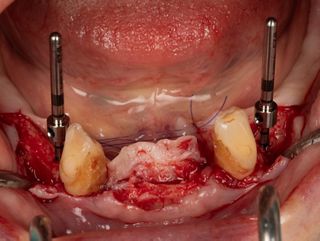

3b. Drilling adjacent to the remaining teeth 33 and 43 using the initial 1.5 mm drill. Depth and axis checked using the anterior indicators and residual canines.

Given the average bone density (D2 to D3), only the initial drill was used to the working length of 12 mm.

3e. Canines 33 and 43 were extracted and the burial of the implants was then checked.

3e